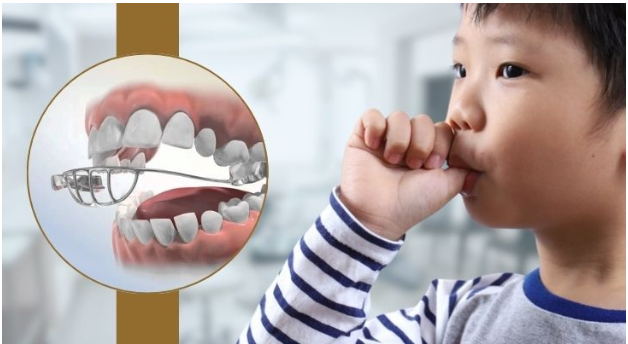

HABIT BREAKING APPLIANCE